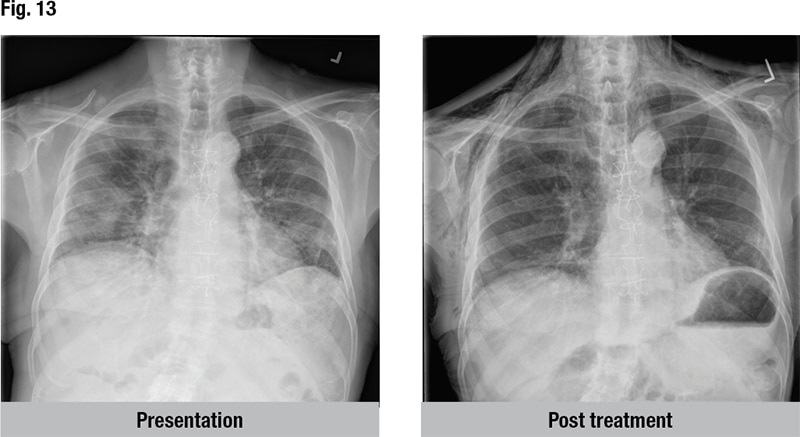

Amiodarone-induced diffuse alveolar damage was the clinicopathologic diagnosis. Dr. Smith pointed to the man’s post-treatment CT scan, which no longer showed infiltrates (Fig. 13). This is what happens, he said, when the patient has an adverse drug reaction that is treated appropriately by stopping the medication and administering high-dose steroids. “The patients do very well. It’s one of the best kinds of DAD you can have, if there is a good kind of DAD to have.”